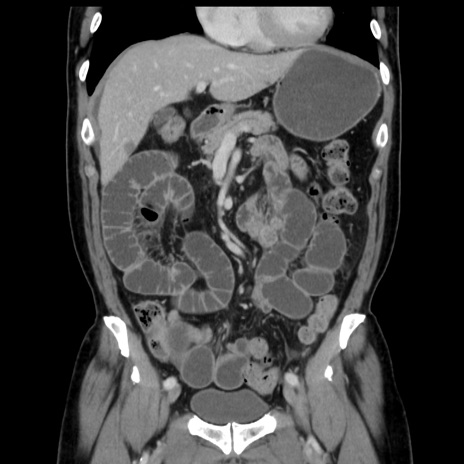

症例16(冠状断像)

【症例】 70歳代男性

【主訴】 腹痛、嘔吐

【現病歴】 約1ヶ月前より間欠的に腹痛と嘔吐あり、当院消化器内科を受診したところCTで多発する肝臓のLDAを指摘され、精査中であった。以降は消化器症状は安定していたが、2日前より嘔気と腹痛があり、同日より排便・排ガスが消失した。改善認めず、 本日、救急外来を受診した。

【既往歴】 大腸ポリープ切除後。

【身体所見】意識清明・会話良好、BT 36.3℃、BP 127/80mmHg、 P 80bpm、腹部:膨満あり、平坦・軟、上腹部正中および下腹部正中に圧痛あり、反跳痛なし、筋性防御なし。

【データ】WBC 7200、CRP 0.77